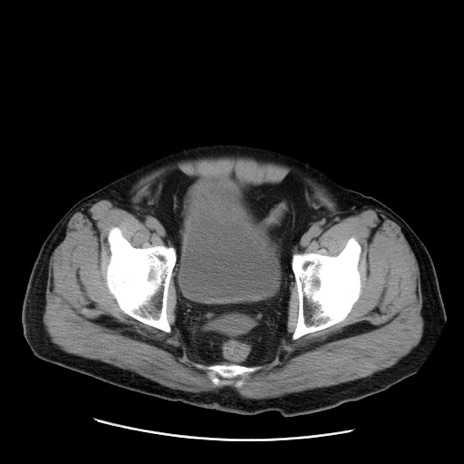

症例20(横断像)

【症例】 60歳代男性

【主訴】 腹部膨満、嘔吐

【現病歴】5日前頃より倦怠感を認め食事量減少し4日前の朝嘔吐、食事摂取困難となった。 3日前近医受診し点滴施行され整腸剤などを処方された。 当日他院を受診し、腹部膨満著明、炎症反応の上昇(CRP10.8、WBC11200)あり、紹介受診となる。

【身体所見】 意識JCS1 受け答えがはっきりしないBP 111/57mHg、 P 67bpm、、BT35.2°C、SpO2 97%(RA)、 腹部:膨隆、打診で鼓音あり、全体的に圧痛有り、腸蠕動音(-)、反跳痛ははっきりせず。

【データ】WBC 11400、CRP 14.20